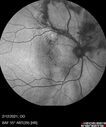

Branch Retinal Vein Occlusion with Venous Macroaneurysm (collateral)280 views66 year old female Did not notice vision loss in the right eye. The right eye has been a little worse than the left but now is much worse. Picked up during annual eye examination. VA had been 20/20 in 5 years ago.

History of brain and spinal cord radiation 1986 for T-cell lymphoma. Now with breast cancer, ablation for tachycardia, HTN

VA OD 6/200, OS 20/32Oct 16, 2021